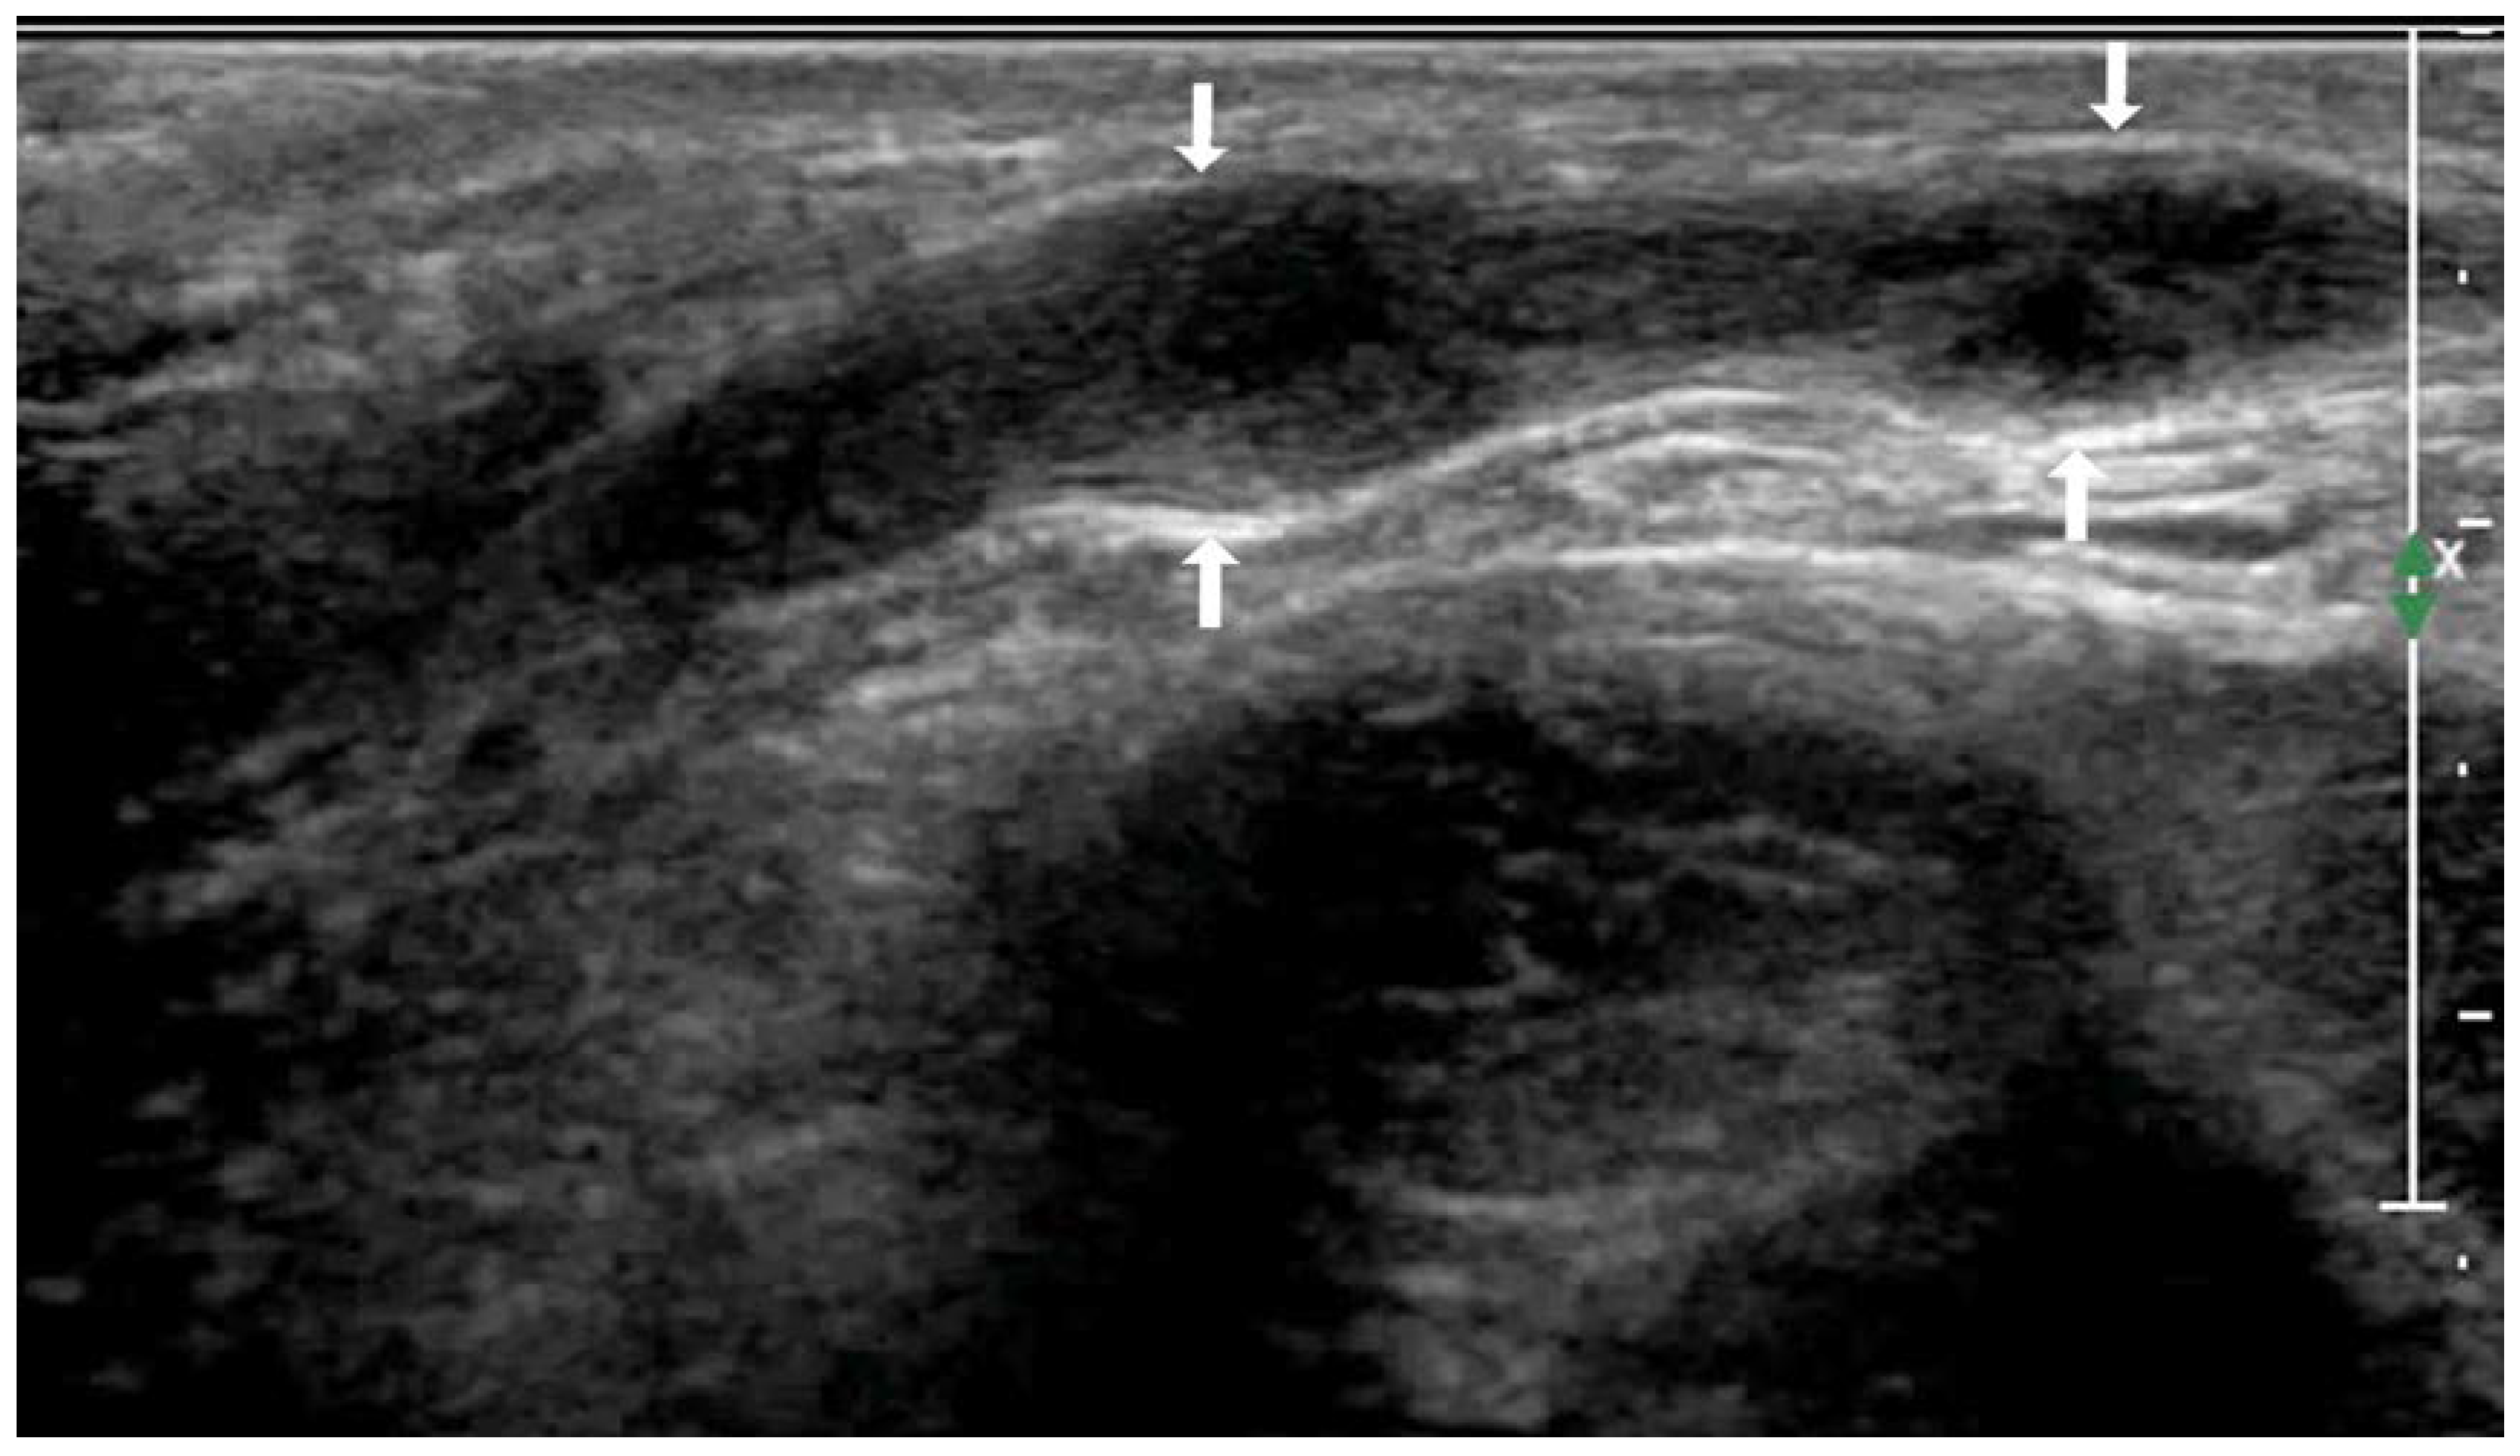

| Lesions conglomeration | + | 10/17 (58.82%) | 6/28 (21.42%) | 6.455 | 0.023 |

| − | 7/17 (41.17%) | 22/28 (78.57%) | |||